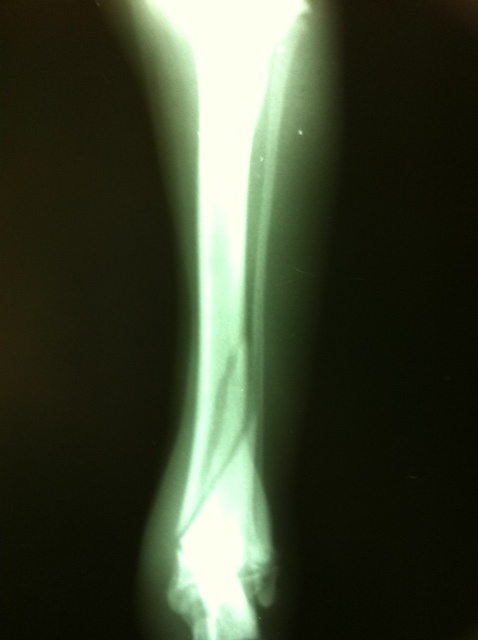

Rumba: triple fractura de tibia.